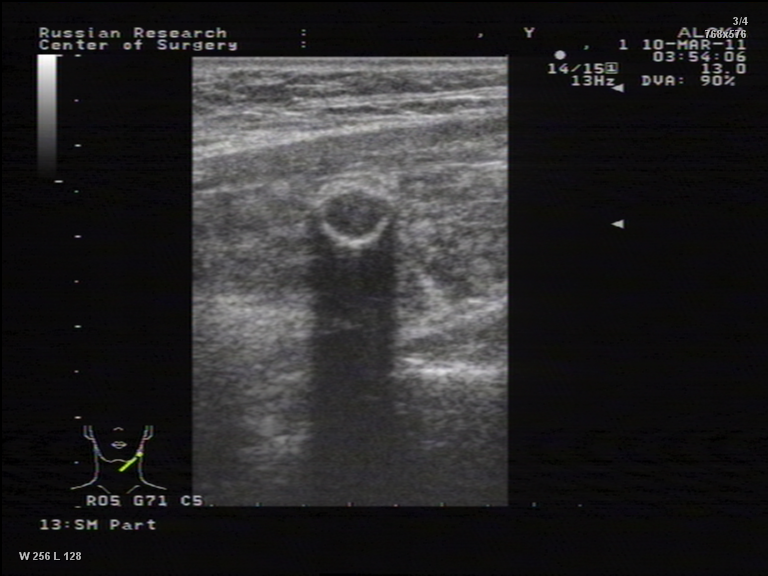

TI-RADS 4. Узлы более 1,0 см в диаметре с “малыми” признаками злокачественности для выполнения ПУНКЦИИ (рис. 3):

- солидные узлы, равномерно или неравномерно умеренно пониженной эхогенности;

- солидные узлы изо- или гиперэхогенные, имеющие “малые” признаки злокачественности:

– гипоэхогенные включения;

– округлая/шаровидная форма;

– неравномерно утолщенное хало;

– макрокальцинаты.

Рис. 3. TI-RADS 4: а – узел шаровидной формы, с ровными и четкими контурами, умеренно пониженной эхогенности, с участками более низкого эхо, с макрокальцинатом. Узел окружен тонким хало (фолликулярная неоплазия); б, в, г (поперечное и продольное сканирование левой доли ЩЖ) – изоэхогенные узлы с гипоэхогенными включениями, с четкими контурами, с тонким хало (фолликулярная аденома); д – изоэхогенный узел с гипоэхогенными включениями, с неравномерно утолщенным хало (фолликулярный рак).